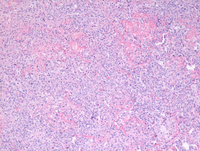

Low power shows patchy and occasional confluent multifocal infiltrates within the lung parenchyma.

Higher power images demonstrate patchy clusters are large atypical cells which are seem to be perivascular/angiocentric (second and third image) with large areas of confluent necrosis.